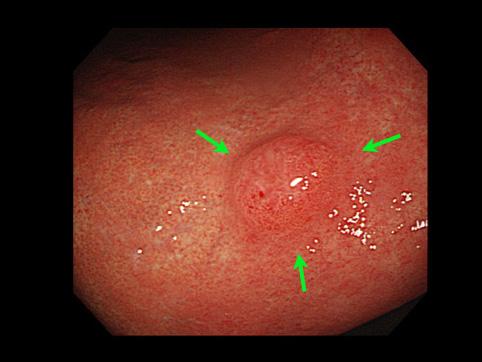

“사마귀”모양의 융기가 다발한 위의 과형성 용종

종양양 병변/과형성 용종

위(부위)/2개 이상

10~14